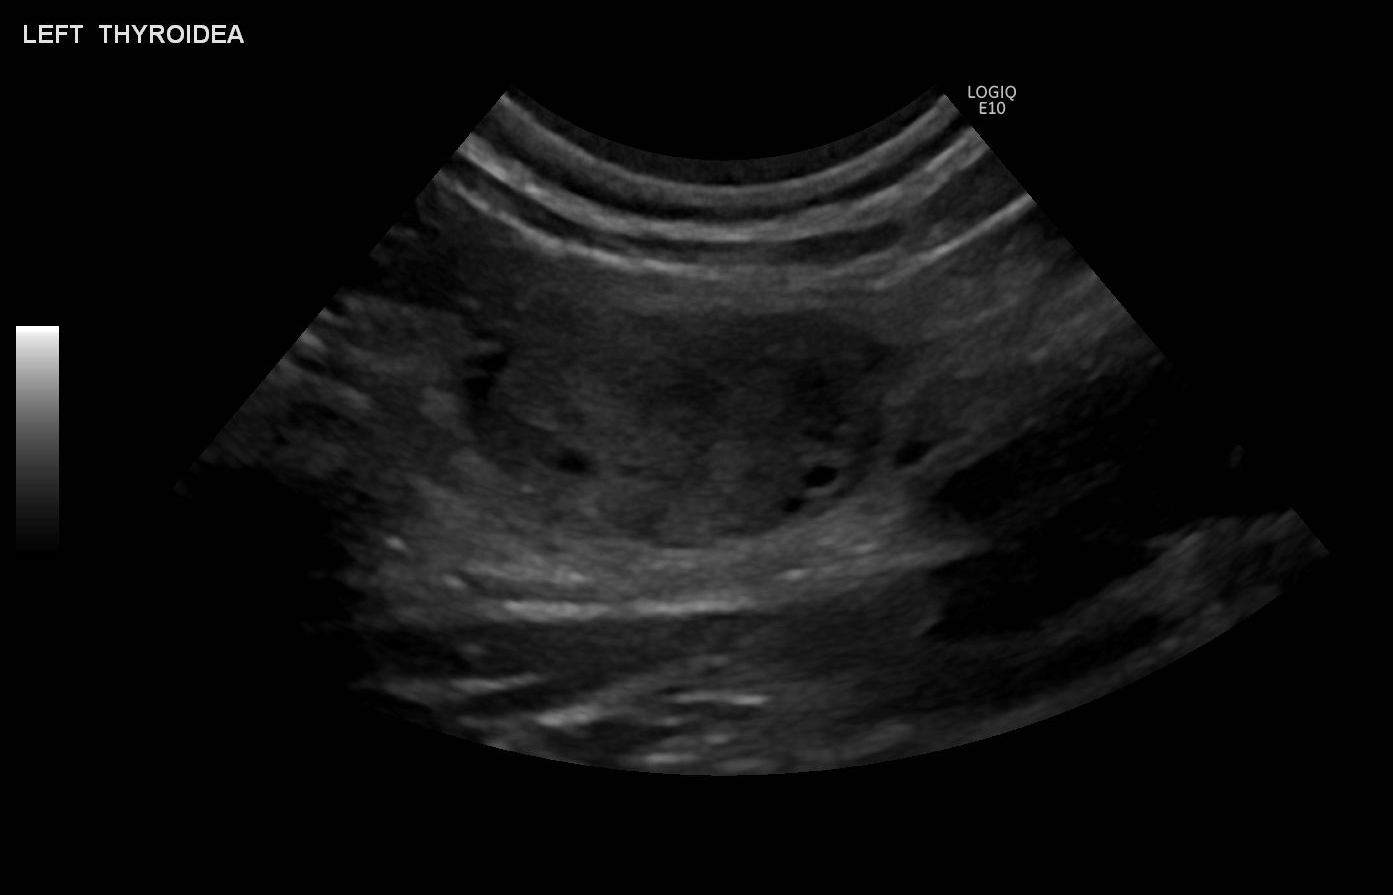

Foto: Klinik für Bildgebende Diagnostik, Universitäres Tierspital, Universität Zürich |

Ultraschalluntersuchungen: Ultraschalluntersuchungen mit geeigneten Schallköpfen ermöglichen eine exzellente Beurteilung von Organen wie der Schilddrüse und den Nebenschilddrüsen. Dabei können Zysten, Knoten und Parenchymveränderungen dargestellt werden.

Ultrasound Examinations: Ultrasound examinations with suitable probes enable excellent assessment of organs such as the thyroid gland and parathyroid glands. They can depict cysts, nodules, and parenchymal changes.